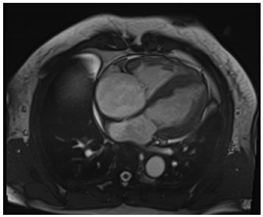

| Cardiac Structure and Function |

| ![]() |

| Cardiac Structure and Function | Dilated ventricular chambers with reduced systolic function in later stages | ![]() |